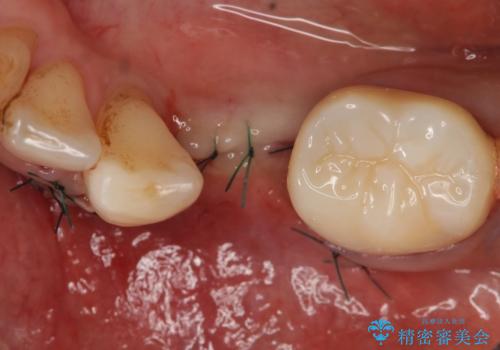

- 左下の歯並びが悪く、左側で物が咬みにくいので診て欲しいといらっしゃった方の症例です。

歯列矯正は御希望されなかったため左下4、5番目の歯を抜歯し、インプラントによる欠損補綴を行いました。

左下6も再根管治療後、オールセラミッククラウンによる補綴を行いました。